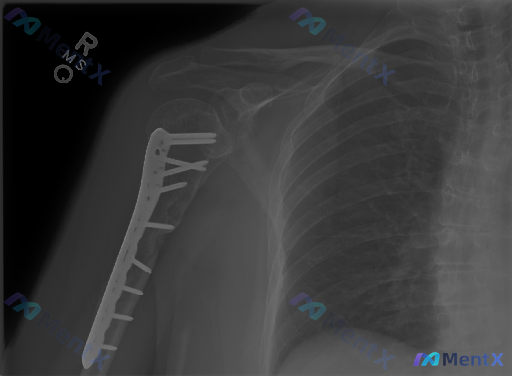

整理了一份右肱骨近端骨折内固定术后的影像资料,想和大家讨论一下读片思路。 先看核心影像表现: - 肱骨近端有金属内固定钢板螺钉系统,位置贴附外侧皮质 - 大结节及外科颈区域可见骨折断端,透亮线存在,部分区域骨痂形成不明显 - 肱骨头与肩胛盂对位基本尚可,肩锁关节、锁骨、肩胛盂未见明显异常 - 周围软...